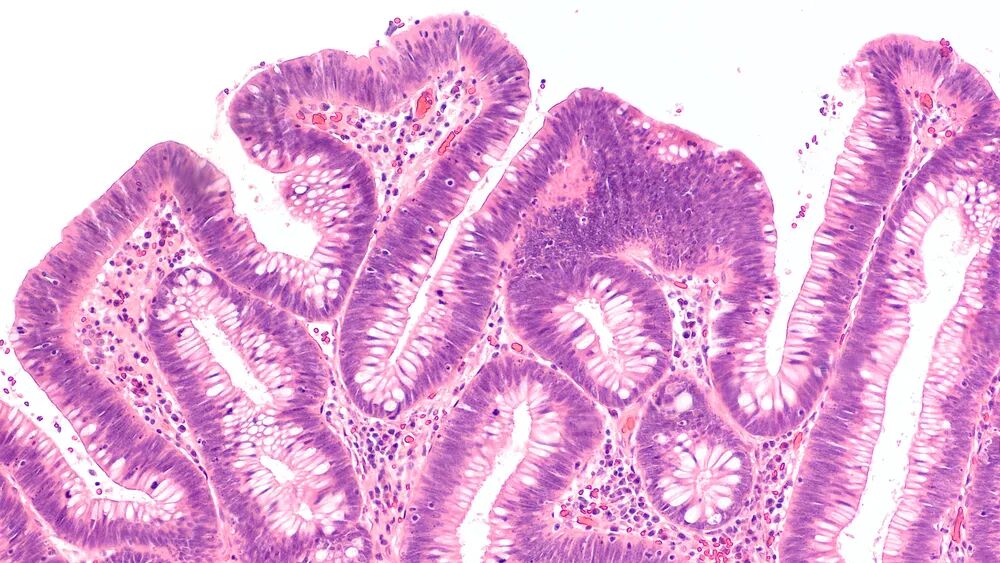

3. 这对父子进行肠镜检查,结果均为多发肠道息肉,且息肉的病理检测结果均为管状腺瘤,这种病情是否严重?

图片来源:站酷海洛